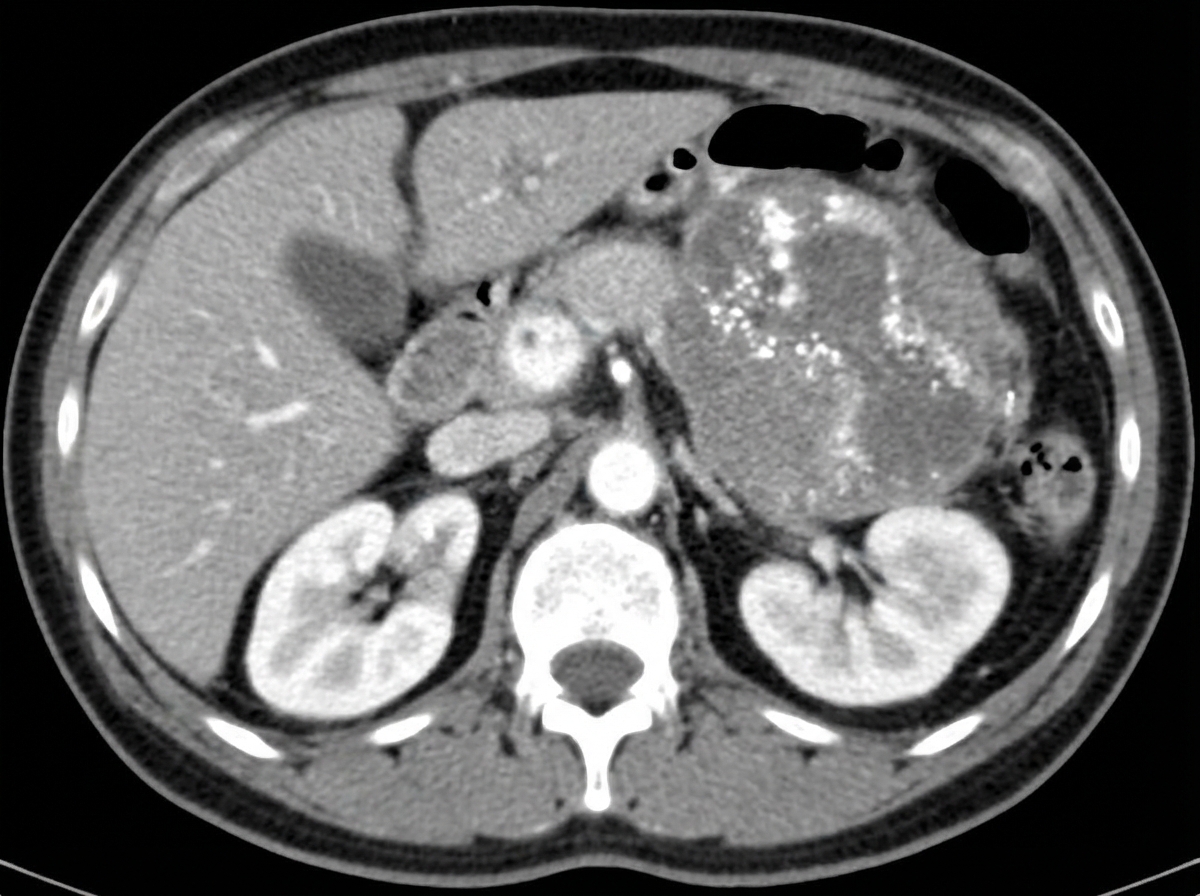

Explanation: ***Neuroblastoma*** - Classic **suprarenal location** with **calcifications** on imaging and ability to **cross the midline**, distinguishing it from other pediatric tumors. - Most common **extracranial solid tumor** in children, often presenting with **abdominal mass** and elevated **catecholamine metabolites** (VMA, HVA). *Histiocytosis X* - Typically presents with **lytic bone lesions**, **skin rashes**, and **pulmonary infiltrates** rather than solid abdominal masses. - More commonly affects **older children** and has characteristic **Langerhans cells** with **Birbeck granules** on histology. *Rhabdomyosarcoma* - Usually arises from **soft tissues** like head/neck, genitourinary tract, or extremities, not typically suprarenal. - Imaging shows **heterogeneous soft tissue mass** without the characteristic **calcifications** seen in neuroblastoma. *Wilms tumor* - Arises from **renal parenchyma** itself, appearing as a **well-circumscribed intrarenal mass** that **does not cross midline**. - Typically shows **less calcification** and **cystic components** compared to neuroblastoma's solid, calcified appearance.